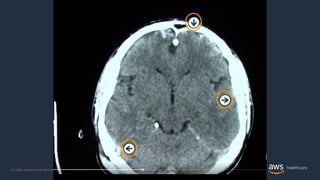

Amazon SageMaker Ground Truth - Rotulagem de imagens médicas

Rotulagem de imagens médicas com Amazon SageMaker Ground Truth

© 2020, AmazonWeb Services, Inc. or its Affiliates. Amazon SageMaker Ground Truth - Rotulagem de imagens médicas Anotações automáticas Dados brutos Anotações humanas Dado de treinamento Anotações humanas

© 2020, AmazonWeb Services, Inc. or its Affiliates. Rotulagem de imagens médicas com Amazon SageMaker Ground Truth